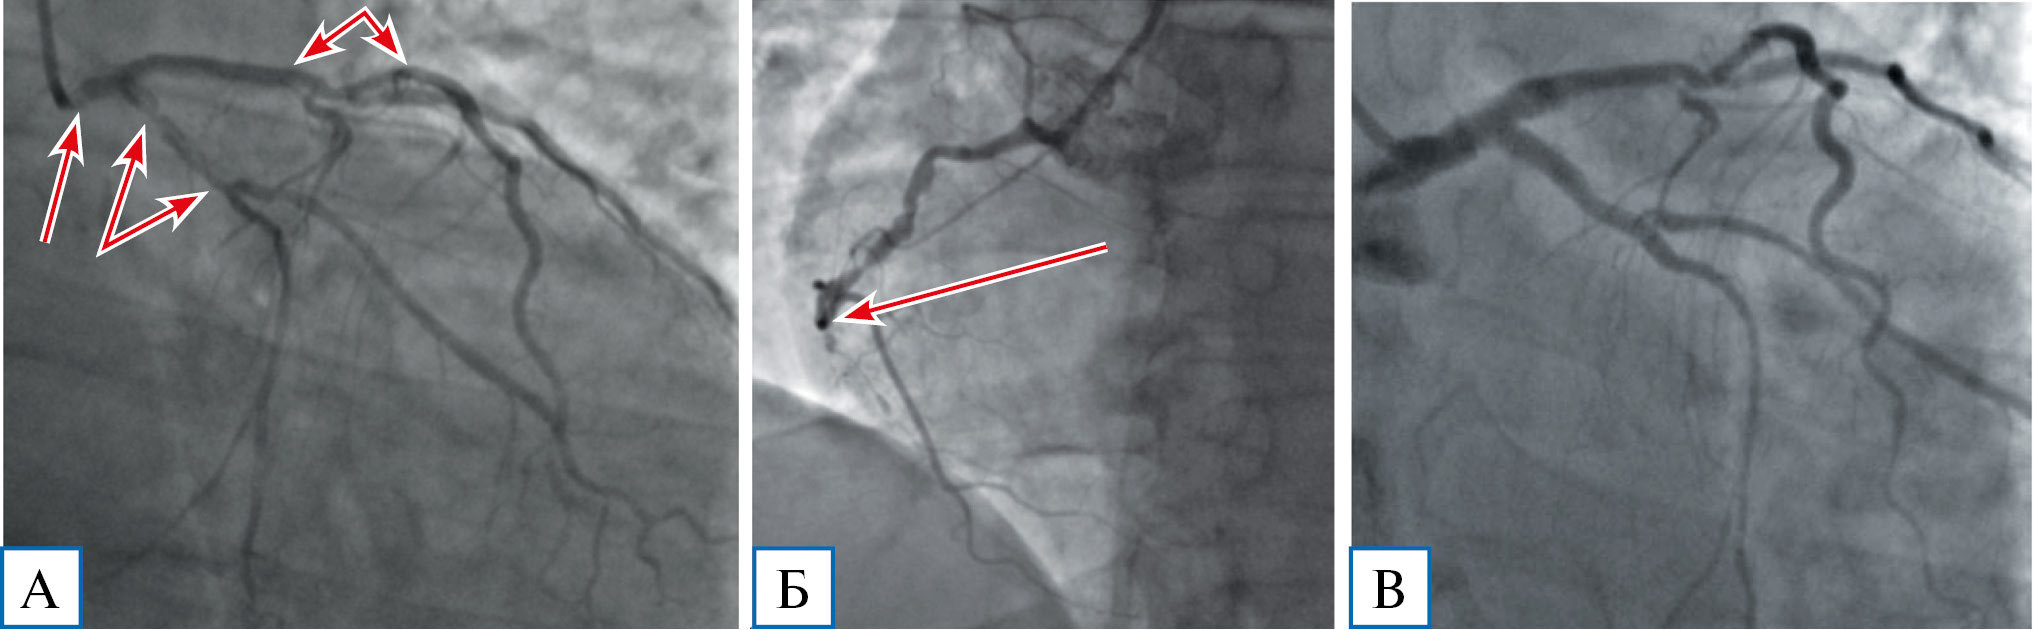

С учетом вышеизложенного было принято решение о необходимости изменения стратегии эндоваскулярного лечения больных острым коронарным синдромом и многососудистым поражением коронарного русла с тяжелой или промежуточной степенью тяжести по шкале SYNTAX, в частности отказ от стентирования только инфарктзависимой артерии в пользу максимально полной эндоваскулярной реваскуляризации коронарного русла, при невозможности выполнения последней — стентирование гемодинамически значимых поражений проксимальных и средних отделов крупных коронарных артерий и/или их ветвей, включая ствол левой коронарной артерии (рис. 3).

Рис. 3. Коронароангиограмма пациента Б. с тяжелым поражением коронарного русла (38 баллов по шкале SYNTAX)

Примечание. А — гемодинамически значимые стенозы проксимального сегмента ствола левой коронарной артерии, проксимального сегмента огибающей артерии и средней трети передней нисходящей артерии (стрелки); Б — окклюзия правой коронарной артерии (стрелка); В — непосредственно после стентирования коронарного русла.

Несмотря на данные существующих исследований и рекомендаций, в условиях COVID-19 данная тактика, вероятно, уменьшила количество больших неблагоприятных сердечно-сосудистых событий у пациентов с тяжелым и промежуточным поражением коронарного русла, в том числе с поражением ствола левой коронарной артерии. Хотя в дальнейшем, скорее всего, будет иметь место увеличение их числа, прежде всего за счет развития рестеноза, и возрастет потребность этих пациентов в аортокоронарном шунтировании, что требует дальнейшего наблюдения.